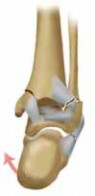

1. Direct access to the posterior malleolus fracture (

TECH FIG 5A

) can be obtained through the posterolateral approach to the fibula (

TECH FIG 5B

).

1. The interval between the Achilles and the peroneal muscle is developed (

TECH FIG 5C

2. The flexor hallucis longus is taken off the fibula down to the interosseous membrane, and then the rest of the deep posterior compartment is taken off the posterior tibia (

TECH FIG 5D

TECHNIQUES B TECH FIG 5 • Direct posterior plating is well

---

C

suited for fractures involving large portions of the posterior malleolus.

A.

Postreduction lateral radiograph showing a posterior malleolus fracture involving more than one third of the articular surface.

B.

Patient in prone position, incision between Achilles and posterior fibula border.

C.

Access is via the interval between the flexor hallucis longus and the peroneal muscle belly. D. Posterior malleolar fragment following A D fibular plating. POSTERIOR MALLEOLUS FIXATION 1. If an adequate reduction can be achieved via closed, indirect reduction, the fracture can be stabilized with cannulated lag screws placed in the anterior-to-posterior direction.